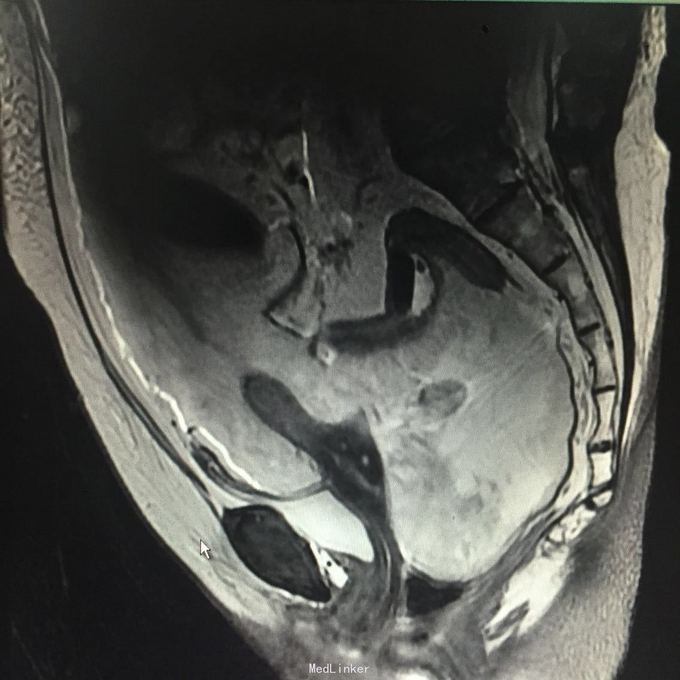

查体:腹围93cm,腹部膨隆,腹肌紧张,全腹部可扪及实性占位,移动性浊音可疑阳性。入院查CA125 472U/ml,HE4 609pmol/l,行B超引导下腹腔穿刺,抽出腹水1000ml,腹水病理:癌细胞。行全腹MR:道格拉斯窝占位性病变,考虑为恶性肿瘤(左侧附件来源),并大网膜、肠系膜、腹膜广泛转移,腹腔大量积液,肝S7/8段包膜下异常灌注灶。

入院诊断:盆腹腔肿物。行剖腹探查术,术中见,腹腔积血500ml,全腹及盆腔簇集状分布大量烂肉样赘生物,腹膜厚,表面密集分布肿瘤组织,子宫及双附件封闭,未探及,考虑手术出血风险大,与患者家属沟通后,暂予以行姑息治疗,遂予以行腹式盆腹腔肿物部分切除术,术中出血1000ml。术后病理:符合癌肉瘤,结合临床发病部位,考虑为卵巢恶性苗勒氏管混合瘤。术后诊断:卵巢恶性苗勒氏管混合瘤IV期。